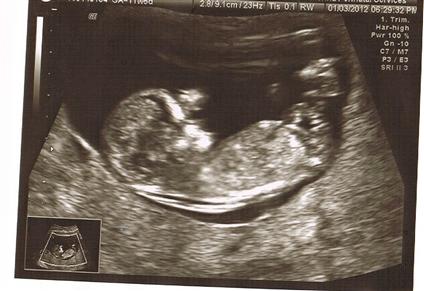

ultrascreen---nub guesses-more pics!

can anyone guess based on this pic? Image Attachment(s):

1st pic, I wish I could see it bigger. Can you upload to your album and then post it again? From what I can see here, I think I see a "girl angle" nub, but I really need a bigger pic.

Hmm, not much bigger, but I think what I'm looking at is the nub, and it's definitely at a girl angle! Now, if that's not the nub, all bets are off, lol.